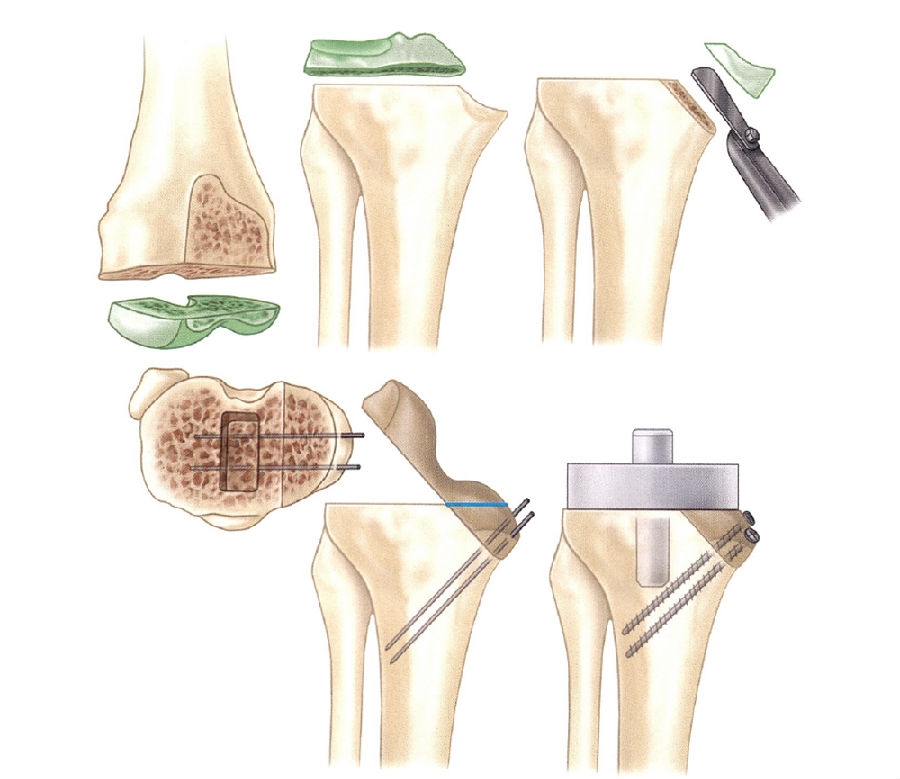

胫骨周围型骨缺损的植骨手术技术:

用骨锯切下尽量少的骨质,将凹陷的、不规则的缺损转变为平整的缺损(图2)。

将自股骨远端或胫骨近端切下的骨块附于平整的缺损处,并用Steinmann针或螺钉固定(图3)。

在胫骨上表面仔细地再次截骨,做出一个平整的表面。

在用骨水泥粘接时,可预先用少量骨水泥封闭移植骨与胫骨的连接部,以防最终用骨水泥固定假体时骨水泥被挤入该间隙内。

若需要从胫骨或股骨上切除过多的骨量才能保证骨面平整对合,则不能采用这种重建方法矫正缺损。在这种情况下,应锉平不规则的骨面,以保证骨移植部位最大限度地对合。

修整移植骨的形状以适应缺损区。

2 Windsor等处理胫骨边缘缺损的植骨方法

3 胫骨内侧节段性骨缺损用股骨远端切下的自体骨填充,用松质骨螺钉固定